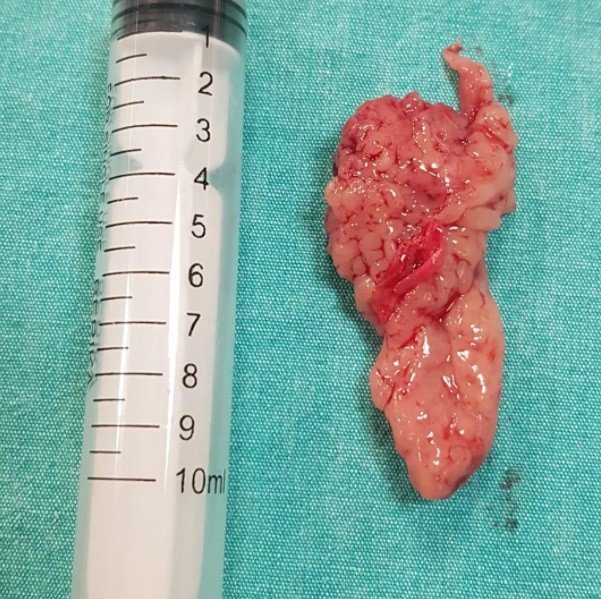

Sivas'ta yaşayan 21 yaşındaki M.T. tek taraflı burun tıkanıklığı, burun kanaması, ağrı ve nefes almada zorluk şikayetleriyle Medicana Sivas Hastanesine başvurdu. Kulak Burun Boğaz Hastalıkları Uzmanı Doç. Dr. Adnan Ekinci'nin hastaya yaptığı tetkikler sonucunda burnunda tümör olduğu anlaşıldı. Hasta biyopsinin ardından kapalı yöntemle ameliyat edildi. Ameliyatta 21 yaşındaki hastanın sol burnundan 10 santimetre uzunluğunda 2-3 santimetre genişliğinde tümör alındı. Konuya ilişkin açıklamalarda bulunan Doç. Dr. Adnan Ekinci, bu büyüklükte bir tümörün normal olmadığını belirterek nadiren de olsa bu şekilde tümörlerle karşılaştıklarını söyledi.

Doç. Dr. Adnan Ekinci, "Vücudun her yerinde tümör görüleceği gibi nadiren de burun içerisinde kanser hücresine rastlanabiliyor. Bize de böyle bir hasta geldi Sivas içerisinden. Hasta da tek taraflı burun tıkanıklığı, burun kanaması ve özellikle ağrı şikayetiyle geldi. Bu tür hastalarda öncelikle detaylı bir burun muayenesi yapmak gerekiyor. Gerekli görüntüleme yöntemi, endoskopi, tomografi, MR çektikten sonra biz bu hastaya burun tümörü tanısını koyduk. Ameliyattan önce biyopsi yapılması gerekiyor öncelikle. Yaptığımız biyopside İnverted Papilloma dediğimiz iyi huylu ama nadiren de kötü huylu kansere dönüşebilen yaklaşık bir 10 santim uzunluğunda bir kitle tespit ettik. Hastamızı da endoskopik yöntemle burun dışında herhangi bir kesi yapmadan direk kamera ile kapalı yöntemle ameliyat ederek hastamızı bu şikayetinden kurtardık "dedi.

Dr. Ekinci, normalde bu büyüklükte bir tümörün olmaması gerektiğini belirterek, "Kapalı yöntem ameliyat olduğu için yaklaşık bir hafta 10 gün içerisinde hasta toparlıyor. Burun dışından herhangi bir kesi veya kırma işlemi yapmıyoruz. Tamamen kapalı yöntemle burun içerisine kamera ve endoskopik yöntemle giriliyor ve tümör çevre dokulardan sağlam sınırlar bırakılarak çıkarılıyor. Normalde hiç olmaması gereken bir şey ama yaklaşık 10 santim uzunluğunda 2-3 santim genişliğinde serçe parmağımızın büyüklüğünde bir tümörle yaşıyordu şimdiye kadar. Kitleyi tamamen total olarak çıkardık ve hastamız şuanda rahatladı" ifadelerini kullandı.